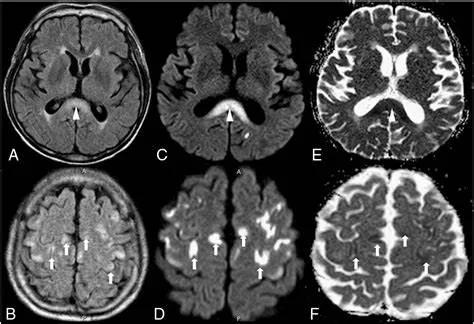

- 急性期表现为胼胝体弥漫性肿胀,T1WI呈稍低信号,T2WI及FLAIR呈稍高信号,以矢状位观察最佳,可单独累及胼胝体压部或整个胼胝体,DWI呈高信号,ADC图呈低信号,部分患者可观察到脑室周围白质或内囊受累,少见皮层受累,表现为扩散受限,不强化和强化病例均可见到。如果增强扫描可见胼胝体有不同程度强化,呈小灶状或不规则斑片状,系血脑屏障破坏所致(如本例),本例患者处于急性期。

原发性胼胝体变性急性期:T2WI矢状位(A)清晰观察到弥漫胼胝体病变,FLAIR呈高信号(B),DWI呈高信号(C),ADC图呈低信号。